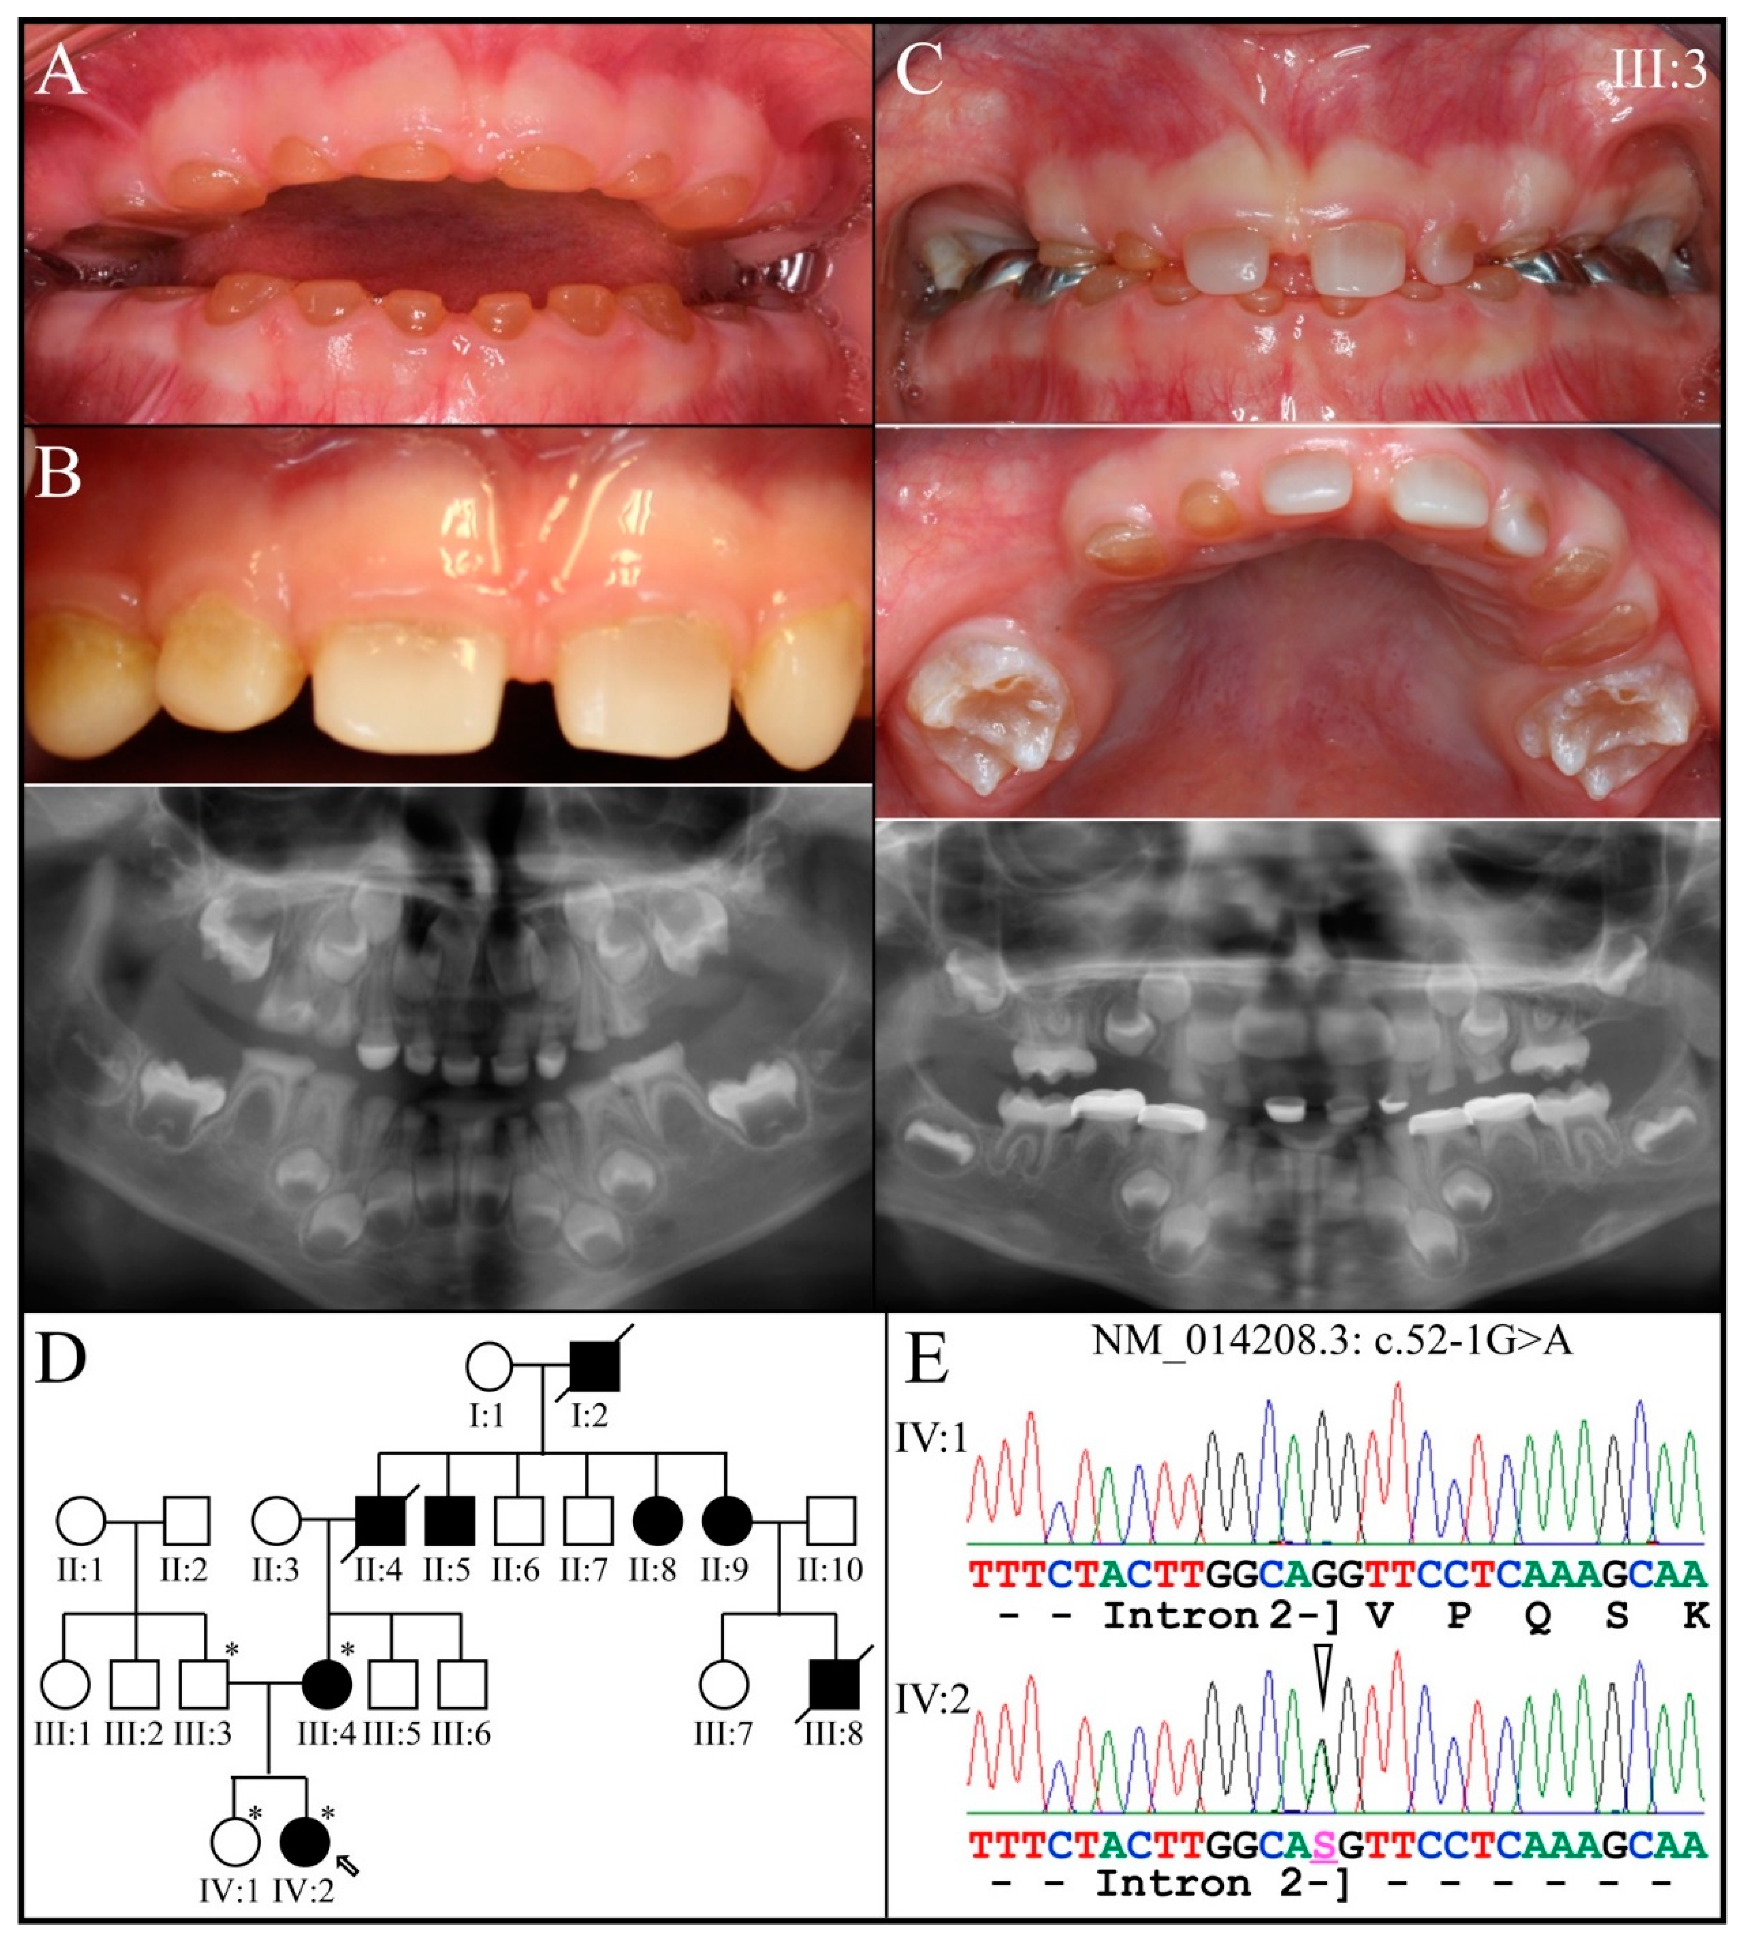

3.3. Eight Families with 3′ DSPP Mutations Causing DD-II or DGI-II

| 11 | Intron 2 | g.8576G>A | c.52-1G>A | p.(?) | Family 2, [69] |

| 2 | Illumina HiSeq 2500 (WES) | NG_011595.1:g.8576G>A; NM_014208.3:c.52-1G>A | Splice Acceptor | IV:2, affected 2nd child: 177.72× |